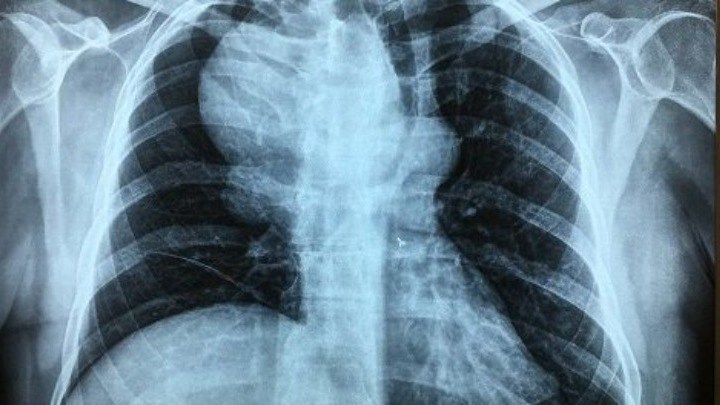

Νέα μελέτη: Οι πολλές ακτινογραφίες και αξονικές τομογραφίες αυξάνουν τον κίνδυνο για καρκίνο των όρχεων

Η πρώιμη και η επαναλαμβανόμενη έκθεση ενός άνδρα σε απεικονιστικές διαγνωστικές εξετάσεις με ακτινοβολίες, όπως οι ακτινογραφίες-Χ και οι αξονικές τομογραφίες, μπορεί να αυξήσουν τον κίνδυνο καρκίνου των όρχεων, σύμφωνα με μία νέα αμερικανική επιστημονική έρευνα.

Διαπιστώθηκε ότι υπήρχε σημαντική αύξηση κατά σχεδόν 60% του κινδύνου για την εμφάνιση του συγκεκριμένου καρκίνου για όσους είχαν κάνει τουλάχιστον τρεις ακτινογραφίες και αξονικές τομογραφίες κάτω από τη μέση, σε σχέση με όσους δεν είχαν κάνει καμία. Ο κίνδυνος επίσης ήταν περισσότερο αυξημένος για όσους είχαν κάνει τέτοιες εξετάσεις κατά την πρώτη δεκαετία της ζωής τους, σε σχέση με όσους τις είχαν ξεκινήσει μετά τα 18.